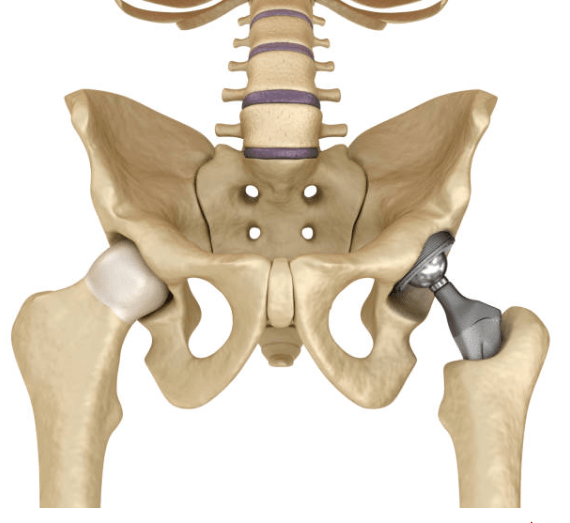

Prothèse totale de hanche sur arthrose

Cette intervention remplace une hanche usée par l’arthrose.

Supprimer la douleur et retrouver une mobilité confortable.

La reprise de la marche est rapide, souvent dès les premiers jours, avec aides à la marche transitoires.

Prothèse totale de hanche sur fracture

Indiquée principalement chez les personnes âgées après une fracture du col du fémur.

Permettre une remise en charge rapide et limiter les complications liées à l’alitement.

Encadrée par une équipe pluridisciplinaire, avec rééducation précoce.